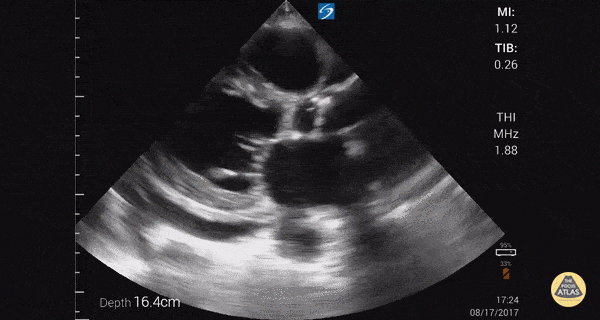

Parasternal long axis with cardiomyopathy, pericardial effusion, and decreased EF. Dr. Gordon Johnson MD Internist Portland Oregon & Uganda